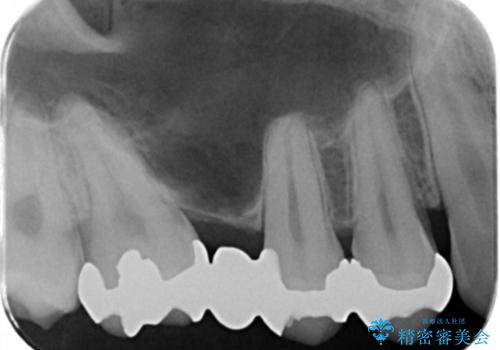

銀のところはインレーブリッジになっており、外してブリッジを入れたいが奥の歯が前に倒れ込んでおり、

ダミーの歯の部分(ポンティック)のスペースが狭いため無理やり作るとインレーブリッジと同じように小さい歯が出来てきます。

なので親知らずを抜歯して、一番奥の歯を部分矯正(upライト)をして倒れ込んでいる歯を起こしてスペースを作り、ブリッジの治療を行いました。